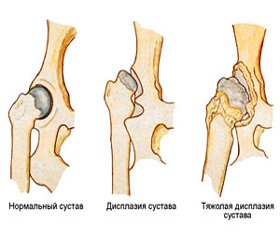

Гипермобильность суставов является наиболее характерным, достоверным фактором и морфологическим признаком ДСТ, которая при других проявлениях патологии соединительной ткани встречается у 10–15 % детей [8, 47, 66].

Гипермобильность суставов диагностируется в зависимости от возраста ребенка. Так, в 6-летнем возрасте она наблюдается у 5 %, а в 12-летнем — у 1 %, чаще у девочек. Учитывая высокую частоту синдрома гипермобильности суставов, его отнесли к ранним признакам формирования недифференцированной ДСТ [67]. Все исследователи согласны с тем, что гипермобильность суставов чаще бывает при генерализованной ДСТ.

Гипермобильность суставов отражает степень тяжести морфофункциональных изменений всего соединительнотканного матрикса, поэтому является главным объективным клиническим тестом в диагностике ДСТ. Гипермобильный синдром нужно рассматривать как причинный фактор многих острых и хронических заболеваний: кифосколиоз, остеоартроз, спондилолистоз, ортопедические деформации скелета [65].

Для определения тяжести диспластической нестабильности суставов Т. Милковска-Димитрова [49] определила степени ее тяжести: 1-я — легкая, наличие 2 главных признаков; 2-я — средняя, наличие трех главных и 2–3 малых признаков или 3–4 главных и 1–2 малых; 3-я — тяжелая, наличие 5 главных и 3 малых признаков.